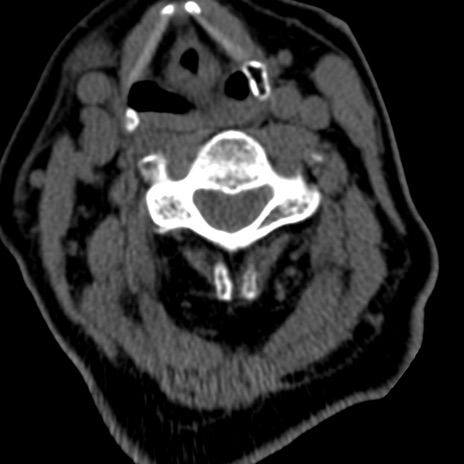

症例50 頚椎CT(横断像)

頚椎CT